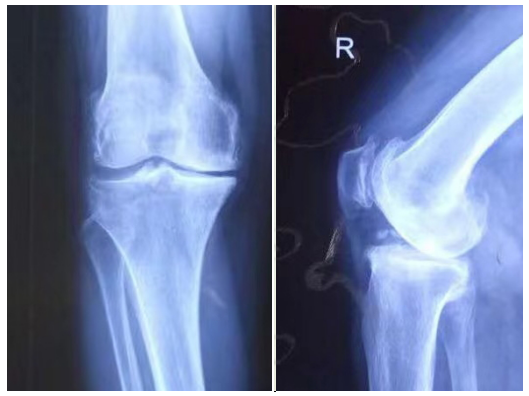

術(shù)前患者的膝關(guān)節(jié)X線片